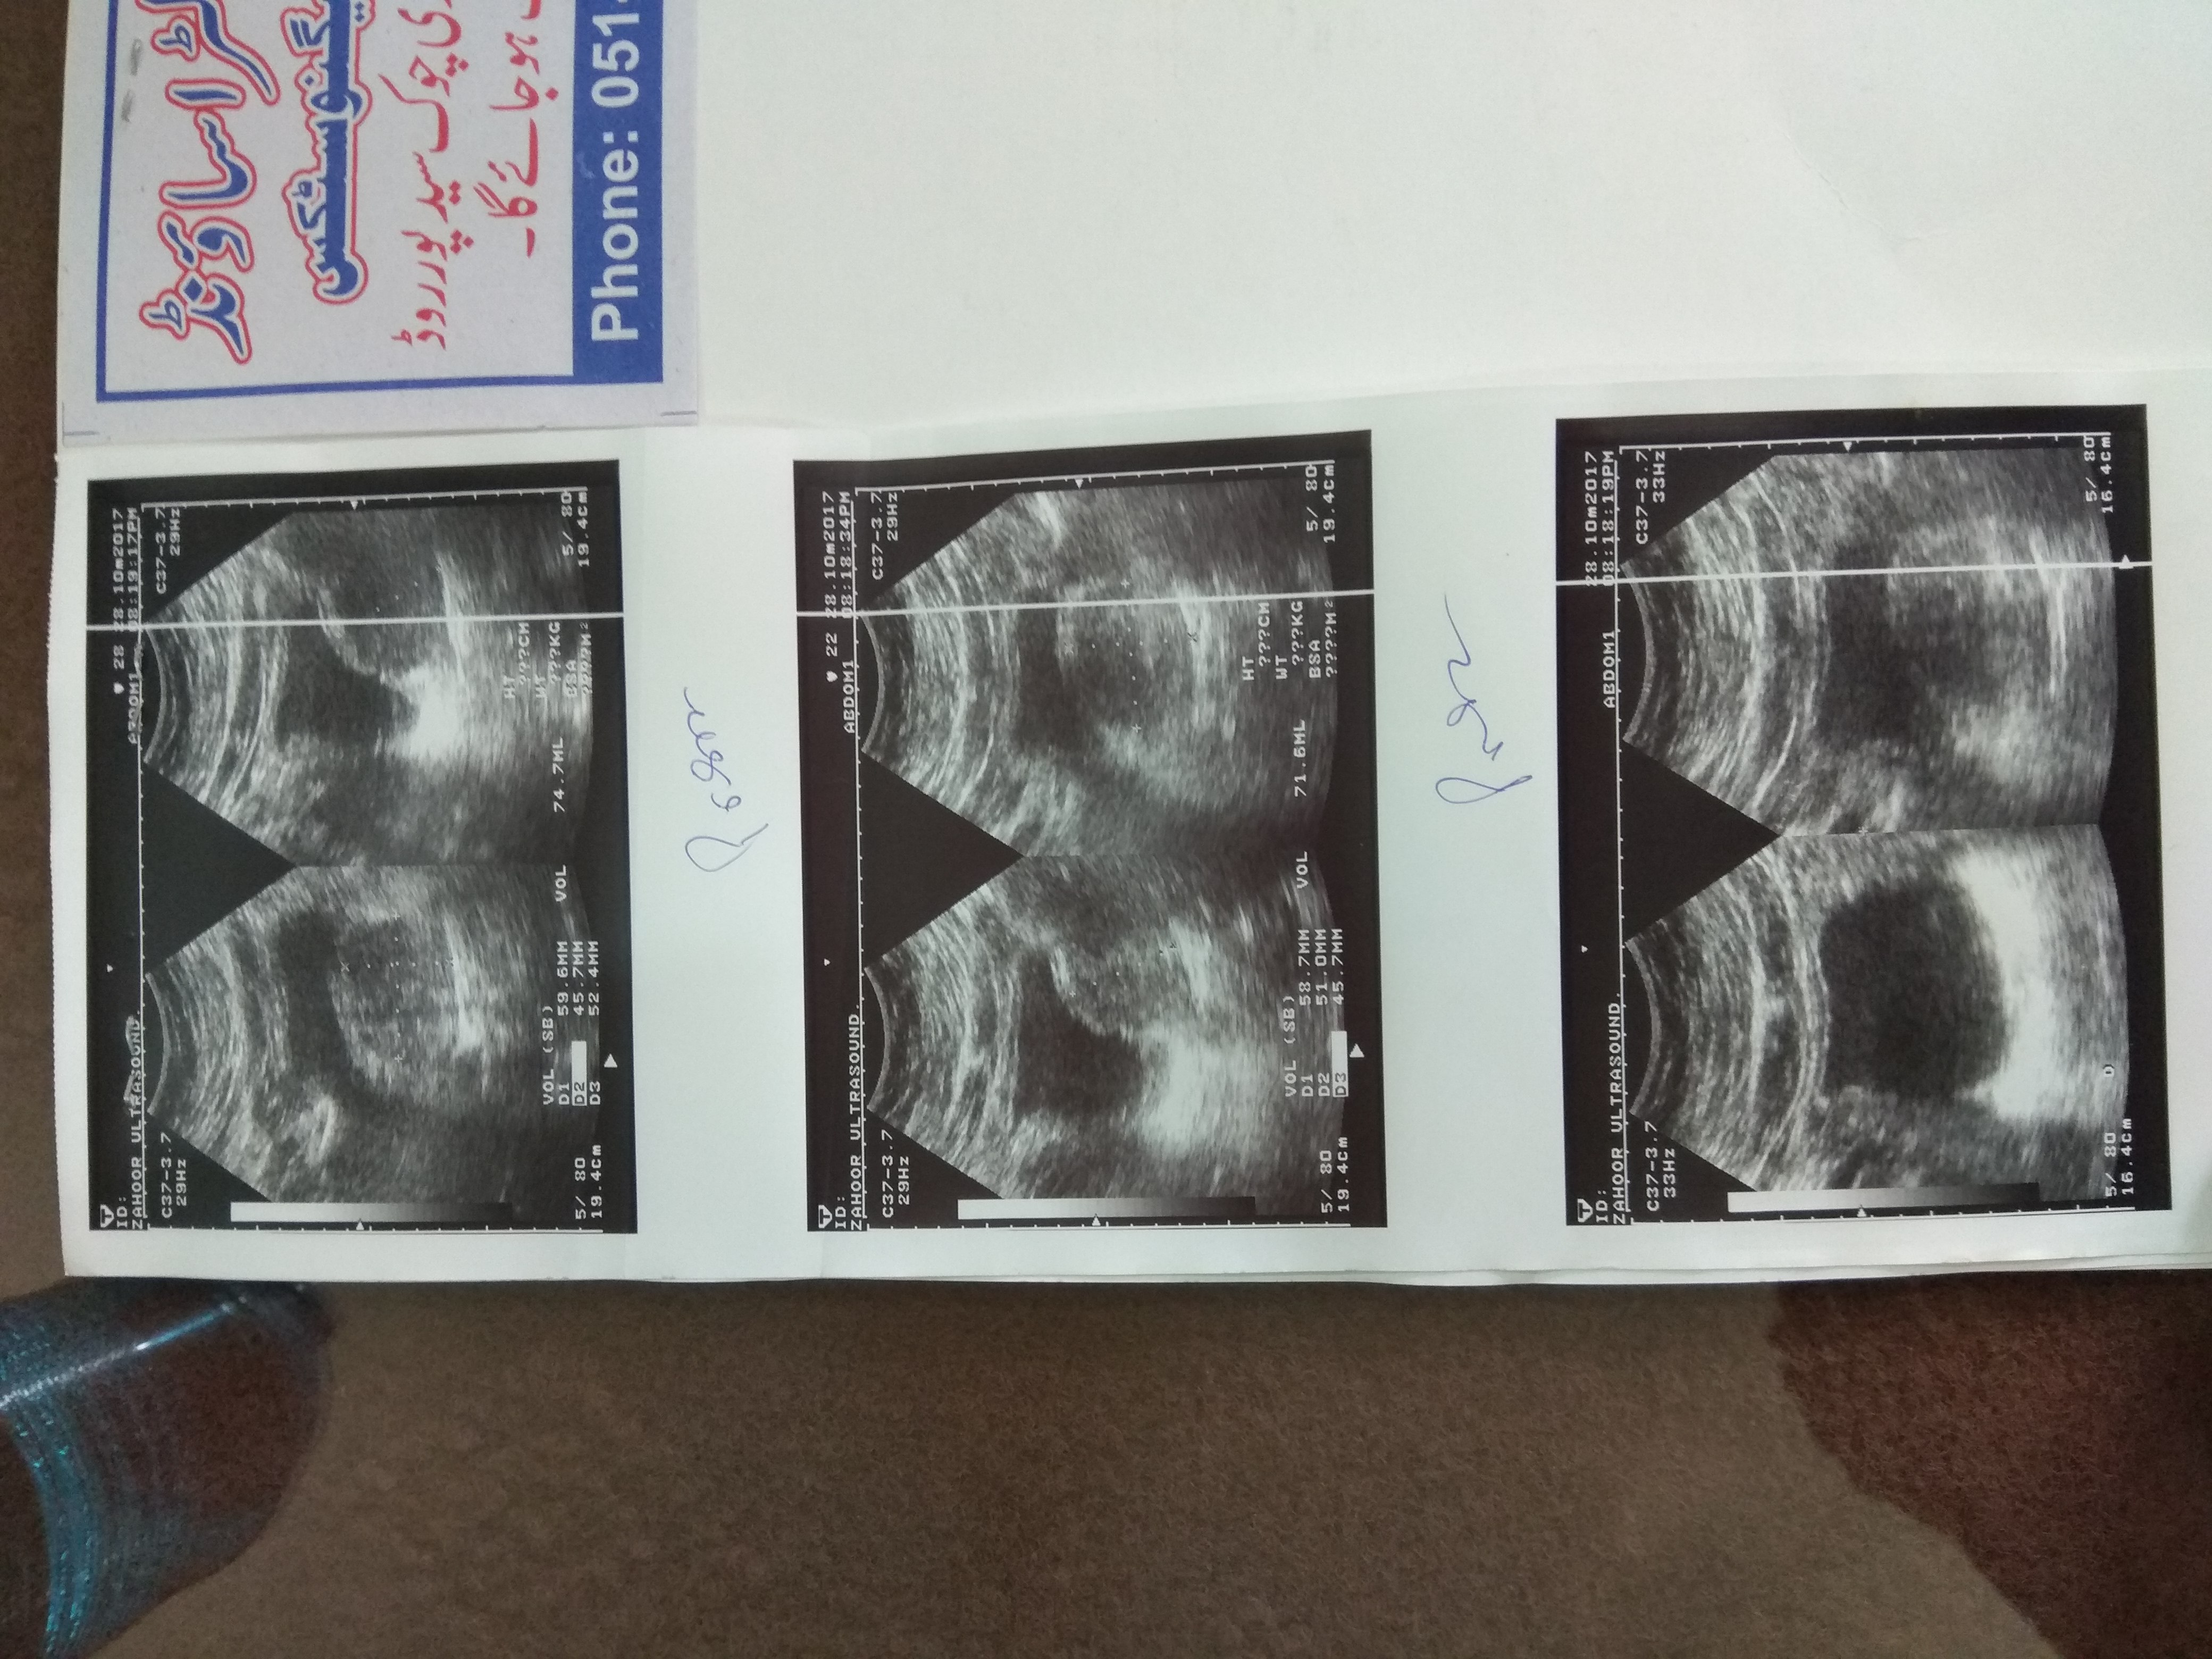

Sir if you have treatment for it somewhere or elsewhere then guide us We are from Rawalpindi. We can come to Lahore or anywhere Reports are attached. Thanks

I think you have an advanced kidney problem and you need to visit kidney doctor for your future management plan .your prescription seems ok but until I see a patient I cannot give suggestions because kidney treatment is an individualized treatment not 1 for all.

Attach Photo here: